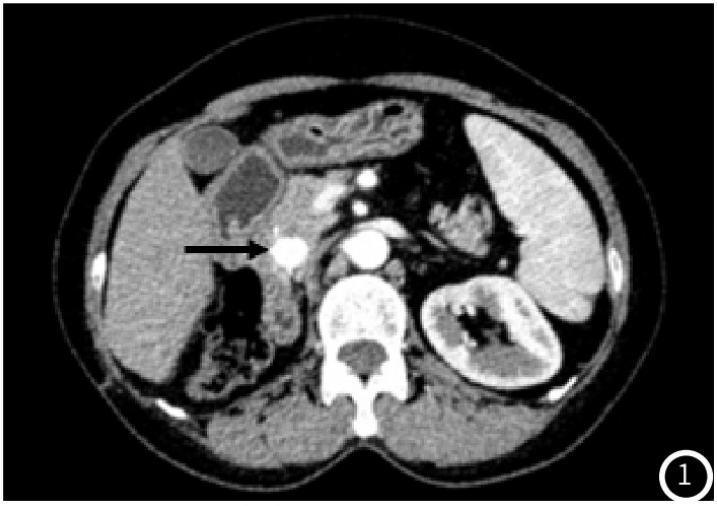

肾癌根治术后6年伴全胰腺转移一例

病例

2025-10-21